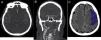

Materiales y métodosRealizamos un estudio observacional retrospectivo. Incluimos pacientes adultos con ACV isquémico causado por la obstrucción de un vaso proximal, diagnosticados mediante angiotomografía en el período de junio de 2009 a diciembre de 2019. Medimos la densidad y el largo del trombo en la adquisición sin contraste, registramos el grado de colaterales leptomeníngeas y la extensión del trombo utilizando el clot burden score. Luego medimos el volumen final del infarto en una tomografía de control y analizamos el grado de correlación entre estos factores radiológicos en el volumen infartado.

ResultadosIncluimos 54 pacientes con ACV isquémico por compromiso vascular proximal; 41 (75%) fueron mujeres. La mediana de edad fue de 82 años. Alrededor del 60% de los ACV comprometieron el hemisferio derecho y el vaso más afectado fue el segmento M1 de la arteria cerebral media (40,7%). Encontramos una asociación entre el grado de colaterales leptomeníngeas (p=0,03) y el clot burden score (p=0,01) con el volumen final del infarto. Tanto el largo como la densidad del trombo no se correlacionaron con el volumen final del infarto.

Materials and methodsThis retrospective observational study included adults with ischemic cerebrovascular accidents due to obstruction of the anterior circulation diagnosed by CT angiography in the period comprising June 2009 through December 2019. We measured the length and density of the thrombus in unenhanced CT images, and we used the clot burden score to record the grade of leptomeningeal collateral circulation and the extension of the thrombus. Then we measured the final infarct volume on follow-up CT and analyzed the correlations among these radiologic factors in the infarct volume.

ResultsWe included 54 patients [mean age, 82 y; 41 (75%) women] with ischemic cerebrovascular accidents due to proximal occlusion. About 60% of the cerebrovascular accidents affected the right cerebral hemisphere, and the most commonly affected vessel was the M1 segment of the medial cerebral artery (40.7%). Final infarct volume correlated with the grade of leptomeningeal collateral circulation (p=0.03) and with the clot burden score (p=0.01). Neither the length nor the density of the thrombus correlated with final infarct volume.